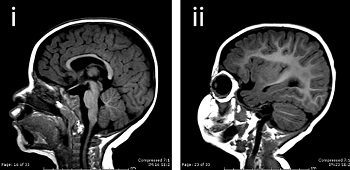

![]() |

| A normal brain and one with microcephaly--Courtesy of Yale University |

Zika hasn't been a priority for vaccine developers until recently because it usually causes mild fevers and rashes; 80% of those affected don't even show symptoms, Reuters reports. But a new flare-up of microcephaly cases in Brazil that is suspected to be linked to the virus has elevated the alarm.